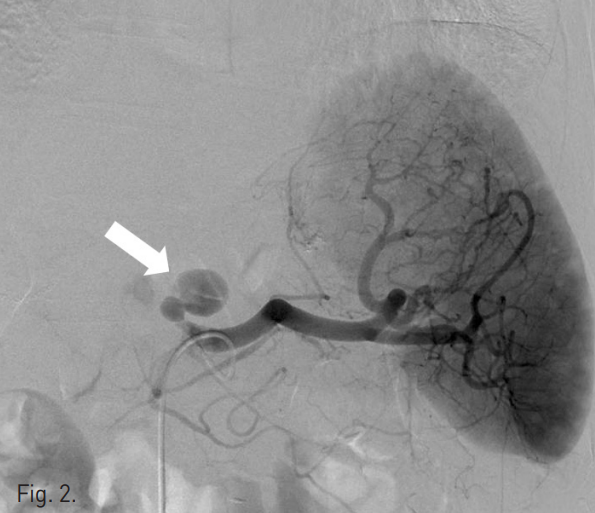

복강동맥조영술에서 비장동맥 근위부에 좌위동맥 잔류부(left gastric artery stump)가 보였으며, 그 끝에서 발생한 가성동맥류가 있다(Fig. 2). 비장동맥에 stent-graft 삽입을 위하여 우측 총대퇴동맥을 통해 8F 65cm long sheath(Teleflex, 회사, USA)를 삽입하였다. Sheath의 tip을 비장동맥 근위부까지 진입시키고 Amplatz stiff guidewire(Cook, USA)를 비장동맥 원위부까지 통과시켰다. 이후 10mm × 4cm stent-graft(S&G, Korea)의 진입을 시도하였으나 stent-graft 시스템이 비장동맥 근위부의 급격한 커브를 통과하지 못하였다(Fig. 3). 총간동맥 조영술에서 잔류위를 공급하는 부위동맥(accessory gastric artery)이나 다른 측부순환로는 보이지 않아 비장동맥 색전술을 시행할 경우 위 경색(gastric infarction)이 우려되는 상황이었으나, 수술을 담당하였던 외과의와의 상의 하에 좌위동맥 잔류부를 포함하여 비장동맥을 코일을 이용하여 색전하였다(Fig. 4). 먼저 10mm × 5cm Standard coil(Cook, USA) 2개를 이용하여 frame을 형성하고 이후 8mm × 14cm Nester coil (Cook, USA) 7개를 이용하여 색전술을 시행하였다. 코일 색전술 도중 코일의 일부가 가성동맥류로 돌출하였으나 좌위동맥 잔류부를 중심으로 비장동맥의 원위부부터 근위부까지 색전하였다. 색전술 후 상장간막동맥조영술에서 미세한 측부순환로를 통해 원위부 비장동맥이 매우 약하게 조영됨을 확인하였다(Fig. 5). 시술 후 12시간에 시행한 CT 조영증강 전영상에서 위벽에 전날 시술시 사용한 조영제가 남아 있는 소견이 보여 잔류위의 관류가 매우 저하되어 있음을 알 수 있었고(Fig. 6a) 비장의 조영증강도 매우 저하되어 있었다. 그러나 동맥기 영상에서 원위부 비장동맥은 조영이 되어 보였다. 시술 7일후 시행한 CT상에서는 위점막의 조영증강은 정상적으로 보였고, 비장에도 다발성의 작은 경색 소견이 보였으나 전반적인 조영증강은 회복된 양상이었다(Fig. 6b). 환자는 시술 52일 후 정상 식이 가능한 상태로 퇴원하였다.

Fig. 2

Splenic arteriogram shows a pseudoaneurysm (arrow) arising from left gastric artery stump which is originated from proximal splenic artery.